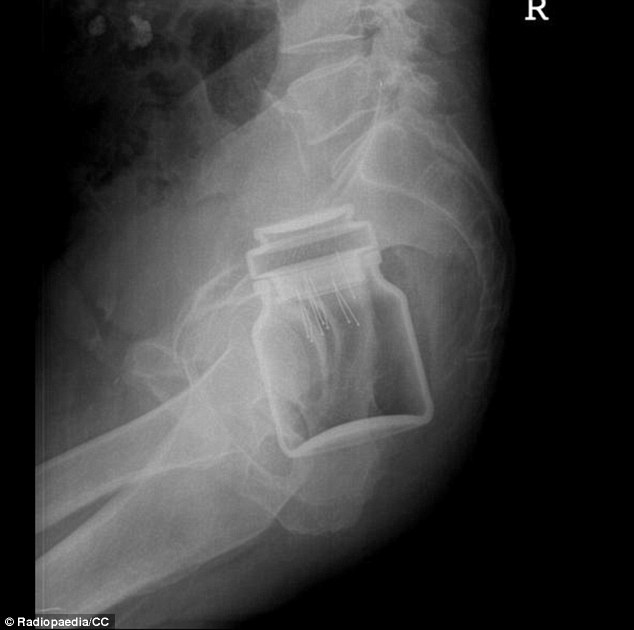

Bác sĩ Lê Thị Kim Dung, Trung tâm Y tế Lao động (Thái Hà, Hà Nội), cho biết đơn vị này vừa tiếp nhận nam bệnh nhân cấy nhiều đinh vít vào "của quý" vì muốn tìm cảm giác lạ.